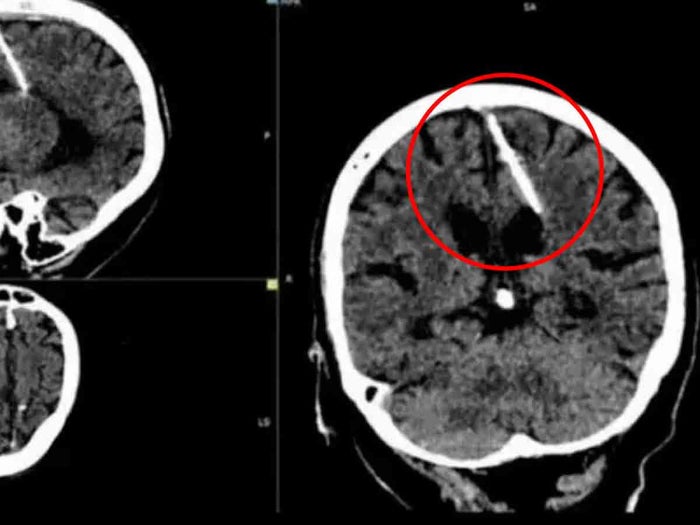

Lo que se suponía que sería un chequeo médico de rutina, se transformó en una sorprendente revelación en Rusia, cuando especialistas descubrieron una aguja de 3 centímetros de longitud en el cerebro de una mujer de 80 años.

Según el informe del Ministerio de Salud, los radiólogos identificaron el objeto durante una radiografía. Este incidente recuerda a un caso previo, donde a un soldado afgano se le encontró un explosivo en su cabeza hace varios años.

Aunque no se han proporcionado detalles precisos sobre el lugar y la fecha exacta del suceso, las autoridades sanitarias han confirmado que la aguja se encontraba en el lóbulo parietal izquierdo de esta mujer. Sorprendentemente, parece que la aguja estuvo en su cerebro desde su infancia, y nunca le causó molestias ni dolores de cabeza.

A pesar del sorprendente hallazgo, los médicos han decidido no extraer la aguja del cerebro de la mujer, ya que no representa un peligro inmediato para su salud.